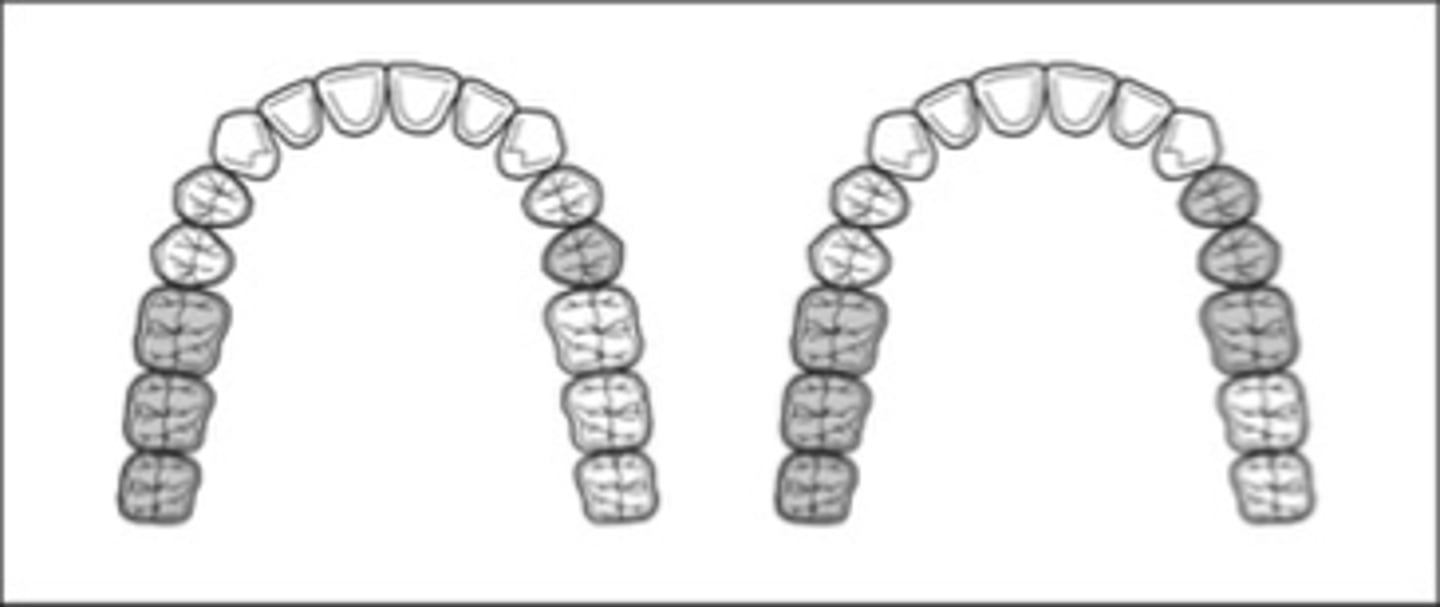

Class I Mod 1

which Kennedy Class?

Class III Mod 3

which Kennedy Class?

Class III Mod 1 (Class I Mod 2 if replacing 2nd molars)

which Kennedy Class?

Class III mod 5

which Kennedy Class?

Class III Mod 2

which Kennedy Class?